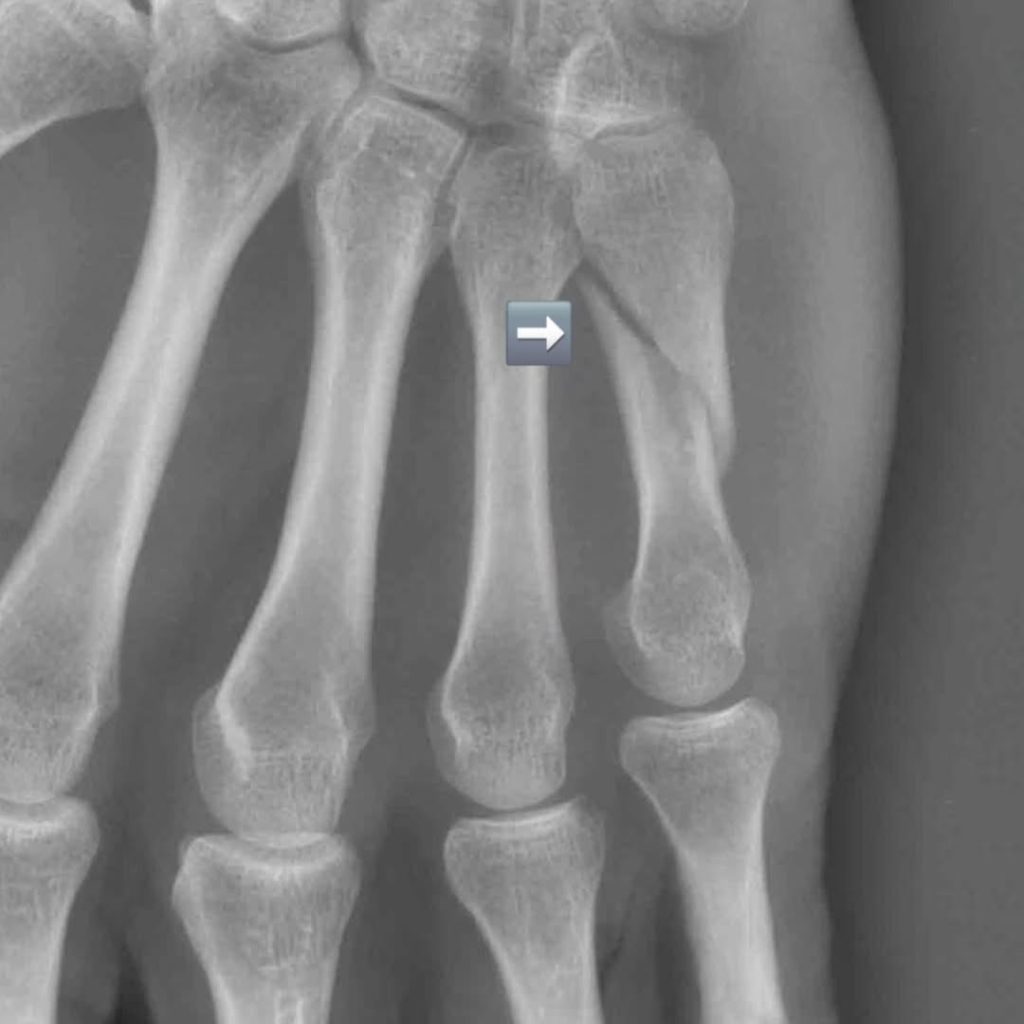

Foi o próprio que revelou que fraturou o “quinto metacarpo aos oito quilómetros de prova”. Nas redes sociais, Pedro Fernandes mostrou-se com o braço imobilizado, revelando ainda imagens raio-X: “Acontece aos melhores. E a mim também.”

Apesar de já ter sofrido quedas em provas semelhantes, garante que “nunca tinham tido grandes consequências”. Desta vez, ao quilómetro 11, escorregou numa zona conhecida como “escadinhas do céu” e acabou por embater com a mão direita nas pedras.